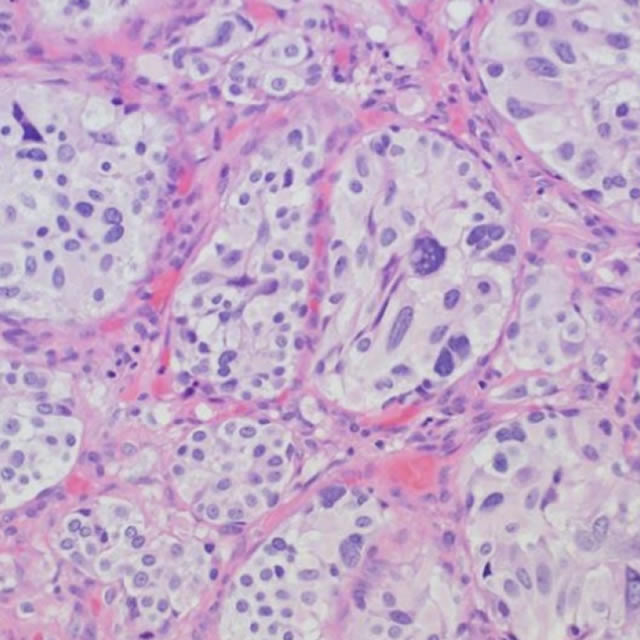

Categorical courses, offering AMA PRA Category 1 Credits™, range from two to five days within the four-week course and provide radiologic-pathologic correlation for both radiology residents and practicing radiologists to show how the underlying pathology of a lesion relates to its imaging appearance.

The mission of these courses is to enable participants to utilize knowledge of how radiology and pathology correlate to improve their diagnostic accuracy in identifying specific diseases, their treatment and potential complications.